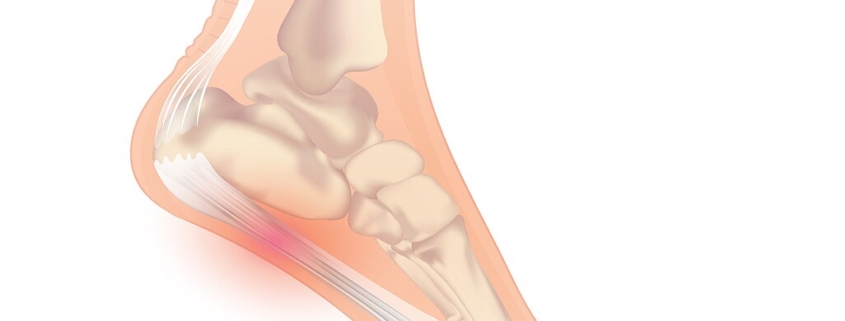

Plantar Fasciitis is a common, and often painful, condition that affects a significant percent of the adult population. Frequently experienced by athletes and individuals who stand for long periods, plantar Fasciitis typically presents pain and stiffness in the bottom (or plantar surface) of the heel.

This condition is caused by inflammation of the plantar fascia – a thick band of tissue that runs across the bottom of your foot, connecting your heel bone to your toes. The discomfort caused by this condition can range from a dull ache to a sharp, stabbing pain, often felt upon taking the first steps in the morning or after a long period of rest.

Plantar Fasciitis arises due to strain on your plantar fascia, leading to tiny tears on the surface and causing it to become inflamed. Risk factors include: